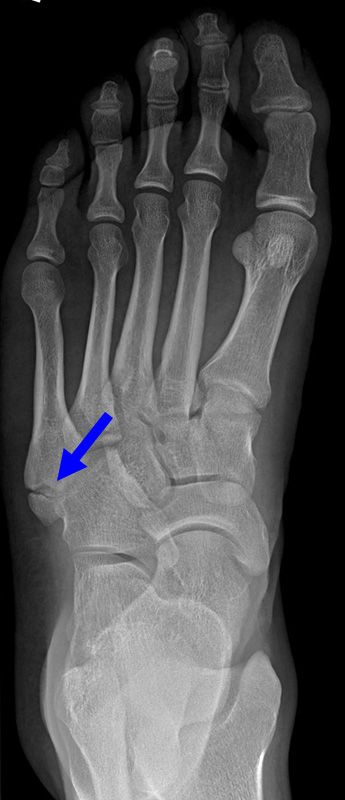

Fuß schräg ohne Belastung (45° Pronationsaufnahme)

Positionierung:

• Der Patient sitzt auf dem Untersuchungstisch.

• Der Fuß steht auf der Kassette, der laterale Fußrand wird um 45° angehoben (optional Verwendung eines Keilkissens).

• Der Zentralstrahl wird auf das Tarsometatarsalgelenk III zentriert.

• Die Röhre ist 0° vertikal ausgerichtet.

Kennzeichen des Röntgenbildes:

• Überlagerungsfreie Darstellung der Zehen und Mittelfussknochen, sowie eine gute Beurteilbarkeit der Fusswurzelknochen.

• Knochenbrücken der Fußwurzelknochen (z.B. Coalitio calcaneonaviculare) lassen sich mit dieser Aufnahme gut darstellen.

• Der Weichteilmantel ist erkennbar.

• Die 45° Pronationsaufnahme wird häufig als dritte Ebene mit belasteten Aufnahmen seitlich und dorsoplantar angefertigt.

Besondere Bemerkungen zum Beispielbild:

• Der Patient erlitt ein Mittelfußtrauma. Unter Frakturverdacht erfolgten die unbelasteten Aufnahmen.

• In der schrägen Aufnahme ist die Frakturlinie im Os cuneiforme I am besten erkennbar.

• Unauffällige Abbildung des restlichen Fußskeletts.

• Für die OP-Planung erfolgte dann noch ein Schnittbildverfahren.